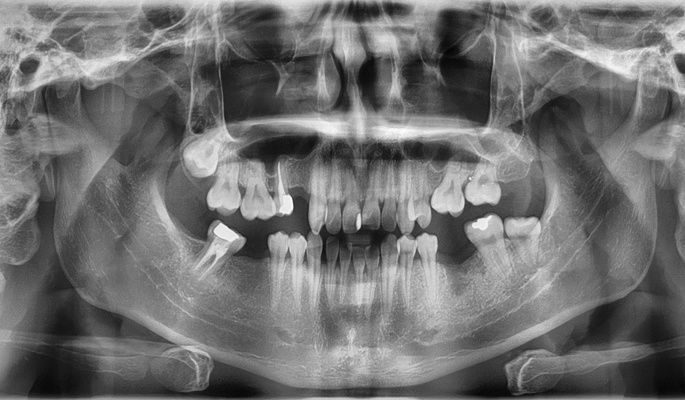

발치 case 1

- 초진

- 양쪽 어금니 심한 우식으로 타치과에서 임플란트 권유받음. 사랑니를 교정치료로 당겨 임플란트 수술 대체함

- 치료중

- 교정으로 이동한 사랑니

- 치료 후

- 교정으로 당겨온 사랑니 10년째 충치 없이 유지 중